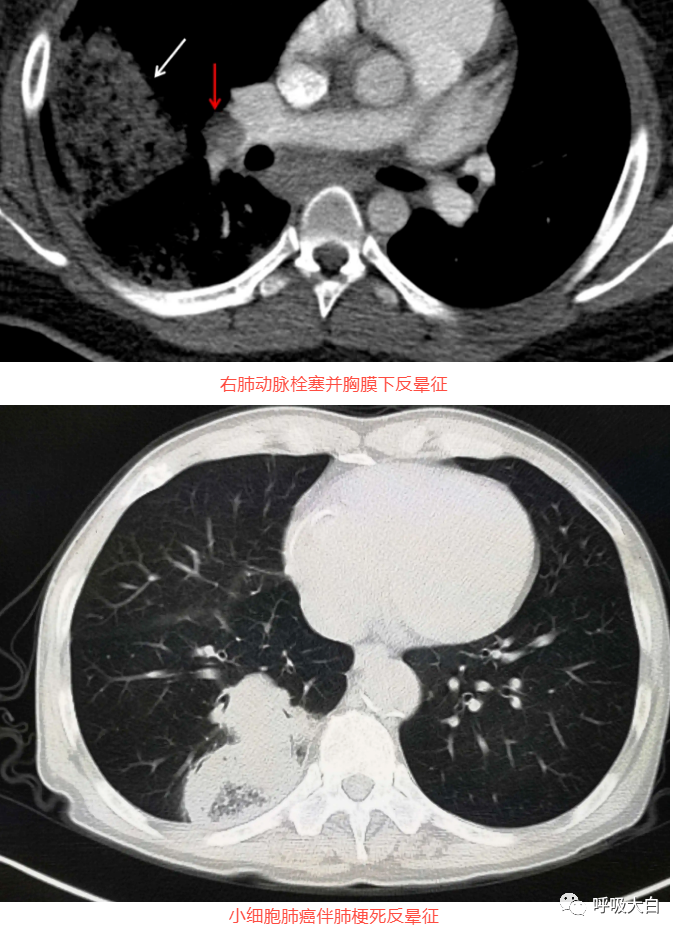

反晕征是一种特殊的胸部 CT征象,表现为环状高密度影围绕着中央密度较低的肺部阴影。起初认为,反晕征为隐源性机化性肺炎的特征性的征象;但此后被报道见于多种其他疾病,如肺副球孢子菌病、肺淋巴瘤样肉芽肿病、肺结节病、侵袭性肺真菌病、活动性肺结核及肉芽肿性多血管炎( 原韦格纳肉芽肿),亦可见于继发于感染或胶原血管病的机化性肺炎。

肺栓塞: